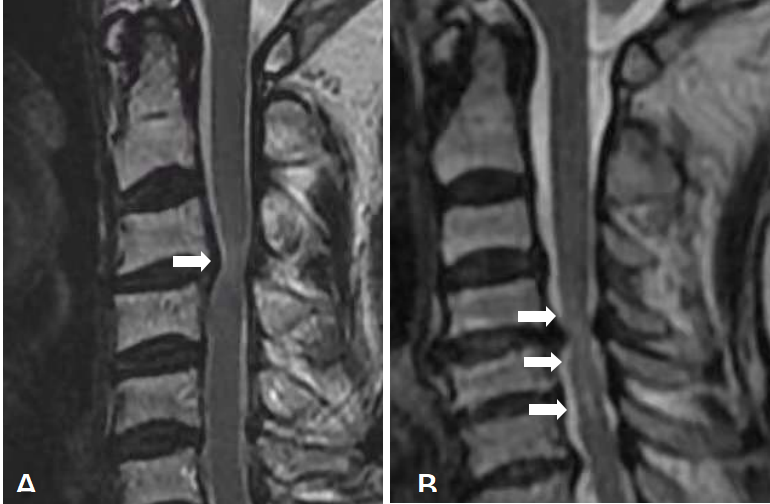

依据Yukawa等提出的评估方法,进行适当修改后,将受压迫节段髓内ISI被评为三度:度,无高信号;1度,轻度且单节段高信号;2度,重度或多节段高信号(图4A、4B)。

图4.髓内高信号分级(ISI)。A:1度ISI,轻度且单节段高信号;B:2度ISI,重度或多节段高信号